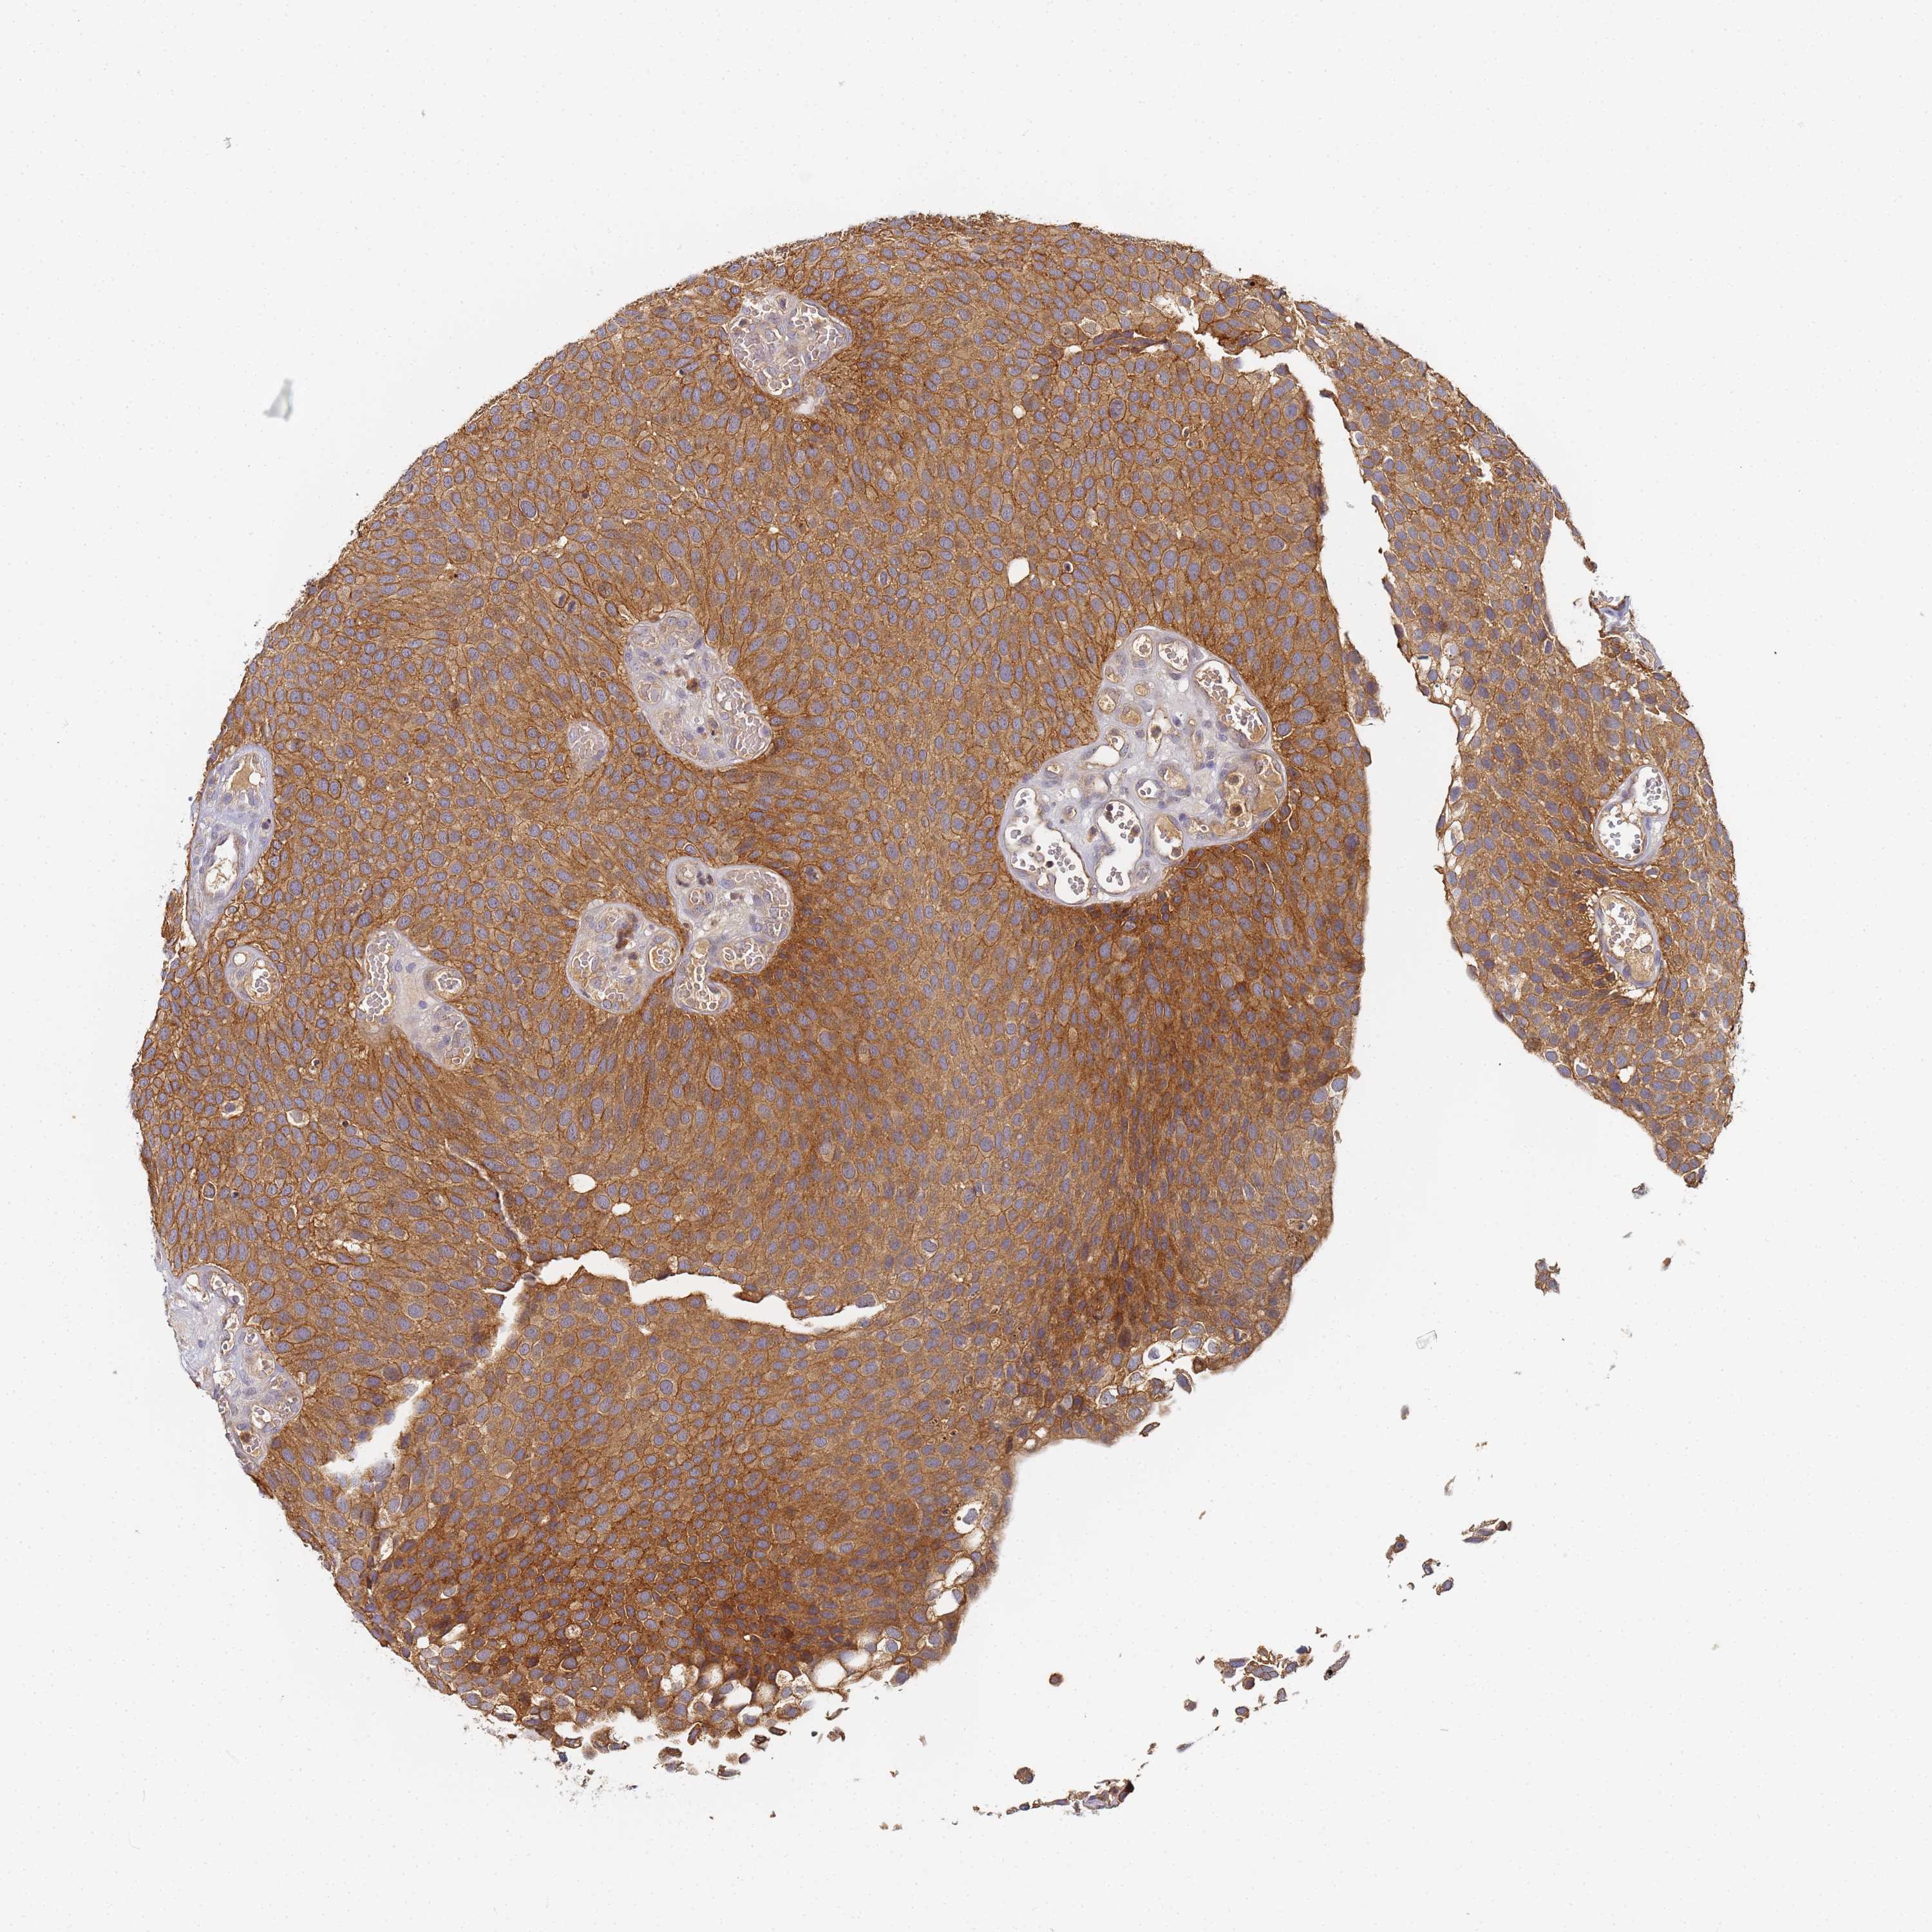

UROTHELIAL CANCER - Protein expressioni

A mouse-over function shows sample information and annotation data. Click on an image to view it in a full screen mode. Samples can be filtered based on level of antibody staining by selecting one or several of the following categories: high, medium, low and not detected. The assay and annotation is described here.

Antibody stainingi

Antibody staining in the annotated cell types in the current human tissue is reported as not detected, low, medium, or high, based on conventional immunohistochemistry profiling in selected tissues. This score is based on the combination of the staining intensity and fraction of stained cells.

Each image is clickable and will lead to virtual microscopy that enables deeper exploration of all samples and also displays staining intensity scores, fraction scores and subcellular localization as well as patient and tissue information for each sample.

Antibody HPA046337

Staining

High

Medium

Low

Not detected

Intensity

Strong

Moderate

Weak

Negative

Quantity

>75%

75%-25%

<25%

None

Location

Nuclear

Cytoplasmic/membranous

Cytoplasmic/membranous,nuclear

Urothelial carcinoma, High grade

Urothelial carcinoma, Low grade